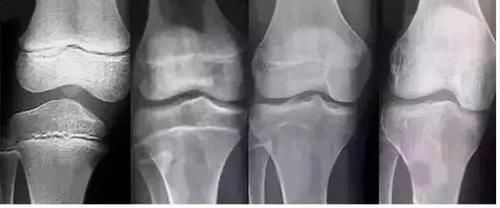

第二天,西西的母亲带着孩子去医院检查,西西虽然现在个子不矮,但是骨龄已经超前发育了,孩子的股侯倩可能会提前闭合,长不了很高了。